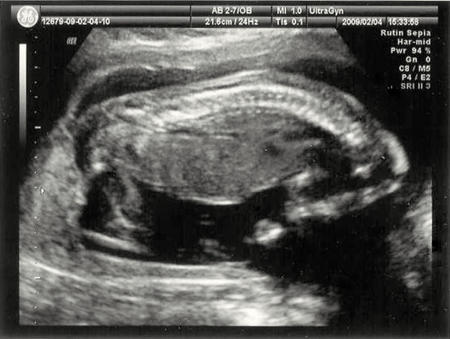

För ett tag sedan fick vi besök av vår son och sonhustru och vi fick då se de första bilderna på vår kommande nya familjemedlem. Vi fick också reda på att det kommer att bli en pojke.

Han var under ... läs mer..